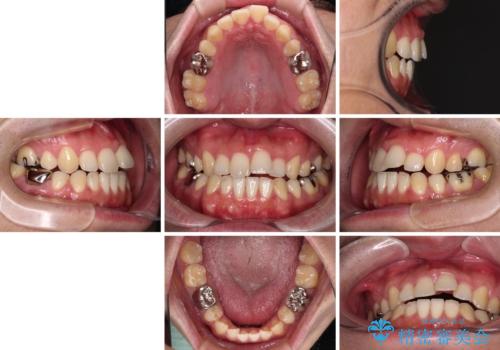

- 抜歯矯正の後戻りを気にして来院された患者様です。

舌の突出癖によるオープンバイトになり、前歯の叢生が後戻りしていました。

舌のトレーニングを行いながら、インビザラインを用いて矯正治療を行うこととしました。

インビザラインの特性を活用して奥歯の咬み合わせを圧下させることで、前歯のオープンバイトを改善さえることができました。